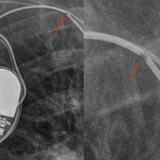

coronary stent

Date: 07/23/2006

Views: 2107